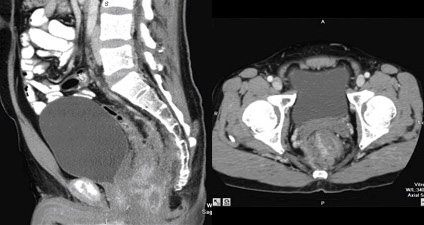

Mr Chia became desperate until a friend recommended him to see me at Mt Elizabeth Hospital. Clinical examination showed Mr Chia to be a well built man in his late 30’s. He was fit and physical examination showed no abnormality except for the huge fixed cancer in the pelvis and rectum. CT films showed gross infiltration outside the rectum and a huge mass was immediately clearly seen. The cancer was clearly not completely respectable at this stage. He was advised to undergo chemotherapy and radiotherapy in an effort to shrink the cancer. This strategy worked well.